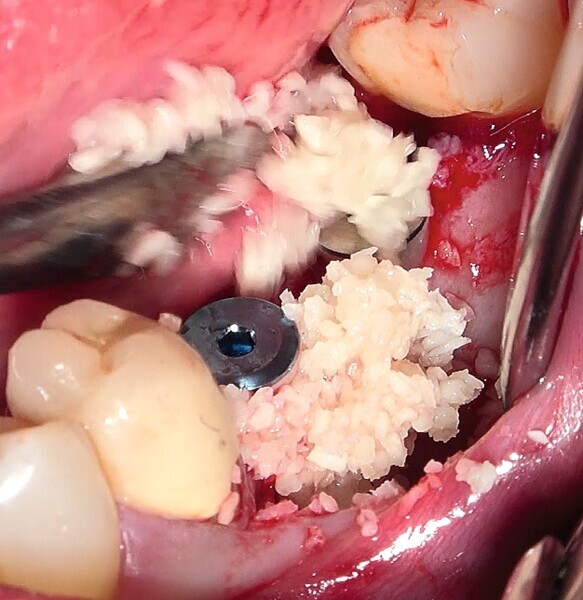

Fig. 29 : Augmentation osseuse latérale (régénération osseuse guidée) au moyen d’une allogreffe constituée d’un substitut osseux, simultanément à la pose des implants.

Fig. 30 : Augmentation osseuse latérale (régénération osseuse guidée) au moyen d’une allogreffe constituée d’un substitut osseux, simultanément à la pose des implants.

La crête alvéolaire au niveau du site de la molaire inférieure était trop étroite pour permettre la pose prédictible d’un implant sans une augmentation osseuse préalable. Des implants deux pièces en zircone ont été mis en place, simultanément à une augmentation osseuse latérale, au moyen d’une allogreffe et d’une membrane de collagène résorbable (Figs. 25–34).